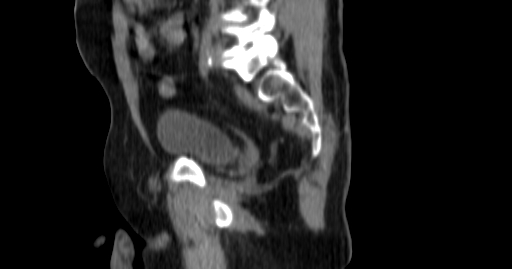

Planning CT Images

Treatment Plan Images

ClearRT® Images